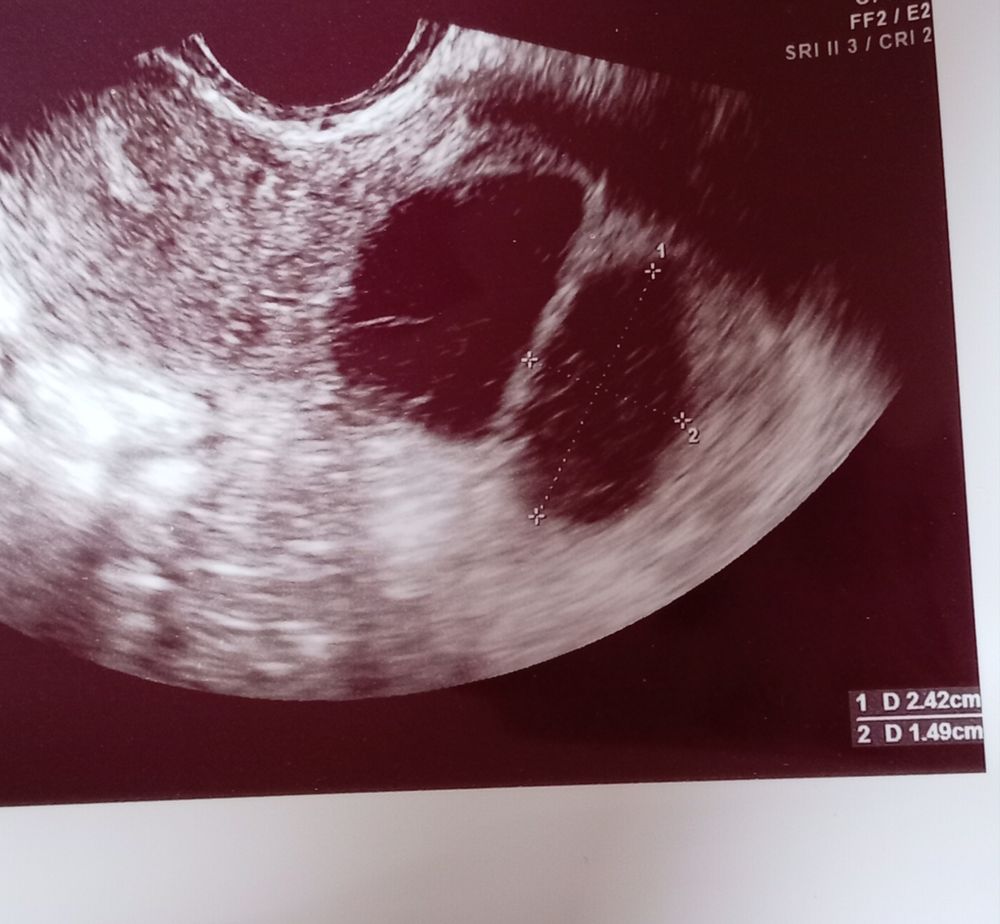

Мама девочки (11 лет), планирую беременность Тбилиси

Мария, я принемала в етом цикле до 9дц так как я почуствала О. Потом пила бм. Вчера на узи на 24дц сказвли 2 кисти 31мм и 24мм а я думаю что ето жт... и ендик 8.1 сказала что тонки... скаала что внутри кист житкость и наверное ето кровь Изображение